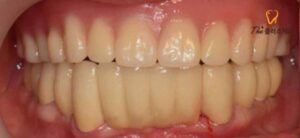

마지막으로 틀니가 완성되어 오면

구강에 맞추어 보고 수정이 필요한 부분을

수정하게 됩니다.

틀니가 마무리되고 난 후에는

하악 전치부 브릿지를 상악 틀니의 교합에 맞춰

소구치까지 연결하여 제작하였고,

환자분께서는 임시 틀니에 비해

불편함이 없고 생각보다 강한 유지력에 만족해하셨으며,

하악 임플란트와 브릿지,

틀니 모두 심미적으로 만족스럽고

교합이 잘되어 식사가 편해지셨다며

감사의 인사를 건네주셨습니다.